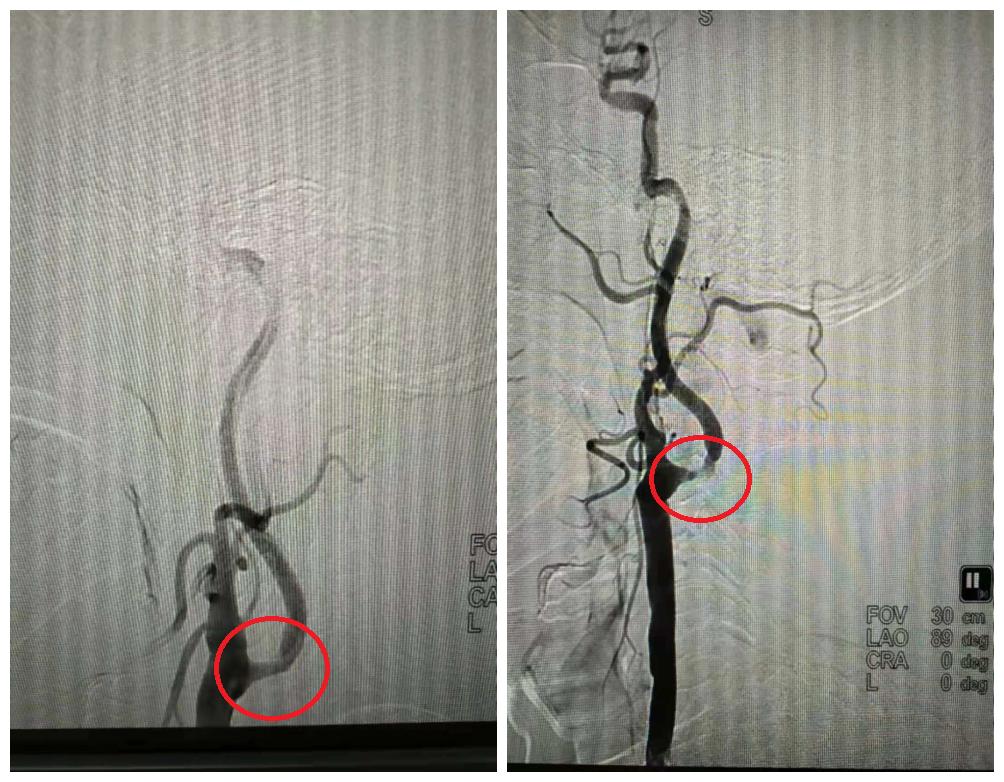

DSA介入治疗

血管球囊扩张成形术和血管内支架植入成型术已经成为治疗脑缺血、脑梗塞十分重要的手段。

手术操作时,在DSA监控下,将导引管经主动脉插到颈动脉或椎动脉(供应颅脑的血管)内,再置放支架,达到扩开狭窄段血管、顺行性血流再建的目的。

DSA介入治疗手术中

芜湖广济医院DSA介入治疗中心,在技术及硬件条件支持下,实现特殊情况下低剂量高清成像,强大高效的临床应用功能助力于各类复杂临床介入手术。